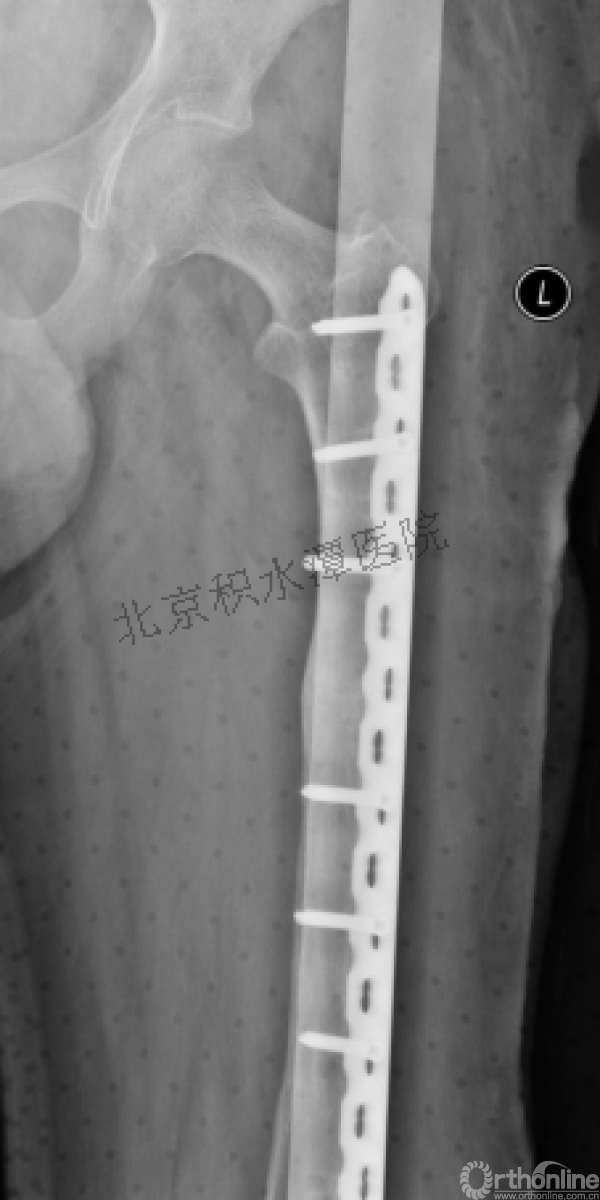

病例分享二

2岁、股骨干骨折,切开+内固定

简单牵引即可!为什么要如此大动干戈?

现实中又是怎样的呢?不知道这属于知识缺乏范畴还是道德品质问题?

匪夷所思!

新生儿股骨干骨折

为什么要手术治疗?

医源性损伤—不愈合!

不具备对儿童骨骼特点的基本了解,不了解儿童骨折的特点,想当然地治疗!